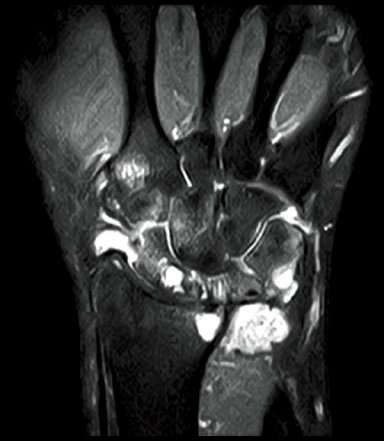

FatSep-T2*WI